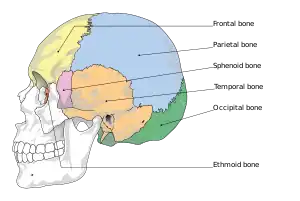

Anatomy

The human skull is anatomically divided into two parts: the neurocranium, formed by eight cranial bones that houses and protect the brain—and the facial skeleton (viscerocranium) composed of fourteen bones, not including the three ossicles of the inner ear.[22] The term skull fracture typically means fractures to the neurocranium, while fractures of the facial portion of the skull are facial fractures, or if the jaw is fractured, a mandibular fracture.[23]

The eight cranial bones are separated by sutures : one frontal bone, two parietal bones, two temporal bones, one occipital bone, one sphenoid bone, and one ethmoid bone.[24]

The bones of the skull are in three layers: the hard compact layer of the external table (lamina externa), the diploë (a spongy layer of red bone marrow in the middle, and the compact layer of the inner table (Lamina interna).[25]

Skull thickness is variable, depending on location. Thus the traumatic impact required to cause a fracture depends on the impact site. The skull is thick at the glabella, the external occipital protuberance, the mastoid processes, and the external angular process of the frontal bone. Areas of the skull that are covered with muscle have no underlying diploë formation between the internal and external lamina, which results in thin bone more susceptible to fractures.

Skull fractures occur more easily at the thin squamous temporal and parietal bones, the sphenoid sinus, the foramen magnum (the opening at the base of the skull that the spinal cord passes through), the petrous temporal ridge, and the inner portions of the sphenoid wings at the base of the skull. The middle cranial fossa, a depression at the base of the cranial cavity forms the thinnest part of the skull and is thus the weakest part. This area of the cranial floor is weakened further by the presence of multiple foramina; as a result this section is at higher risk for basilar skull fractures to occur. Other areas more susceptible to fractures are the cribriform plate, the roof of orbits in the anterior cranial fossa, and the areas between the mastoid and dural sinuses in the posterior cranial fossa.[26]